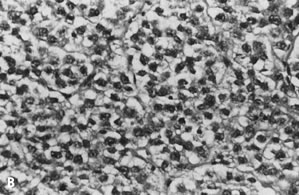

The specific cytomorphologic features of lesions in a variety of body sites will follow; however, general cytomorphologic criteria of malignancy for epithelial lesions are presented here. The most useful diagnostic criterion applied to FNA specimens is cellularity, as nearly all neoplasms (particularly malignancies) yield cellular specimens on aspiration, whereas aspirates of nonneoplastic lesions and some benign neoplasms are hypocellular. Another useful diagnostic criterion is that of architectural complexity within intact tissue fragments. Although the practice of cytology is generally thought to rely entirely on evaluation of subtle cellular and nuclear details, large tissue fragments are often present in FNA biopsy specimens of epithelial lesions and contain valuable information. In general, normal parenchyma and benign epithelial lesions are characterized by architecturally “flat,” two-dimensional fragments with well-organized and uniformly spaced nuclei (Fig. 2A), whereas malignant epithelial neoplasms generally yield complex, three-dimensional fragments with significant nuclear overlap and disorganization (Fig. 2B). Obviously, all cases must be evaluated for conventional nuclear criteria of malignancy, including variation in nuclear size, shape, and chromatin pattern in adjacent cells. In addition, nuclear membrane abnormalities, altered chromatin distribution (including both hypochromasia and hyperchromasia), and elevated nucleus-to-cytoplasm ratios are important features of malignancy in individual cells (Fig. 3).22 General cytologic features of commonly encountered lesions in the breast, lymph nodes, gynecologic tract, and pelvis will be presented.

Fig. 2. ( A) Well-organized, 2D tissue fragment typical of benign glandular epithelium (stain, Papanicolaou) in contrast to ( B) architecturally crowded, 3D tissue fragment from case of adenocarcinoma showing complete loss of cellular polarization and organization (stain, Papanicolaou).